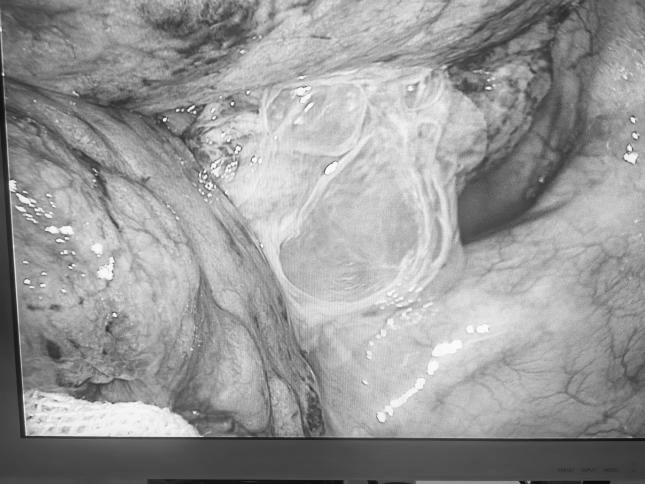

术中见李爷爷胸腔粘连,要耐心细心一点点分离粘连,才能找到破裂的肺大疱。在手术过程中,还需要克服诸多技术难题,如老年人脆弱的心肺功能可能无法耐受麻醉及手术操作打击,肺组织由于高龄顺应性下降,脆性增加导致易出血、肺切缘缝合处针眼易漏气的风险等。在麻醉科主任骆喜宝主任率领的麻醉团队的保驾护航下,吴云飞团队克服重重困难,顺利为老人家完成手术,凭借娴熟的手术和操作,手术时间大大缩短,手术过程短平快,老人家术后 1 小时就回到普通病房,术后 6 小时就恢复进食。